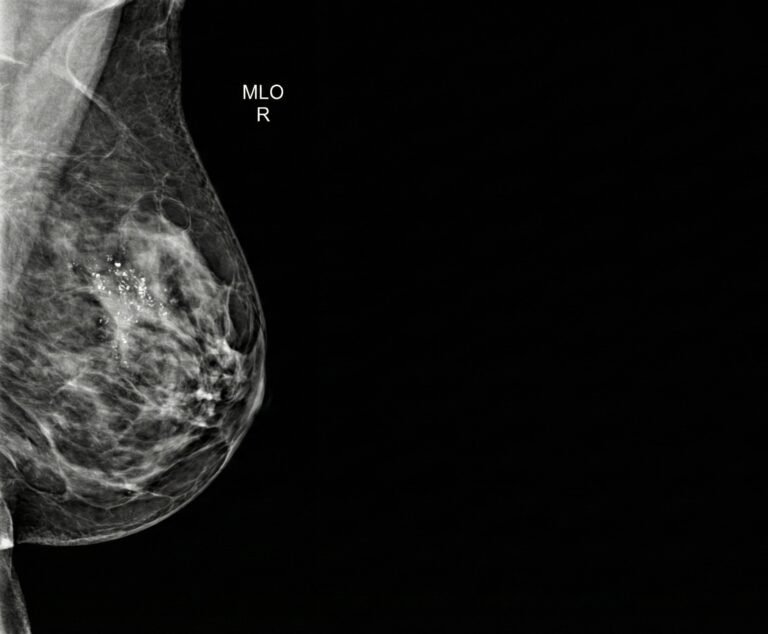

Sono felice di condividere una nuova pubblicazione scientifica di cui sono co-autore, dedicata a un tema molto attuale nella diagnostica senologica: il possibile ruolo della PET/RM con [18F]FDG nella gestione del tumore della mammella in fase iniziale. Il lavoro è disponibile come preprint su…